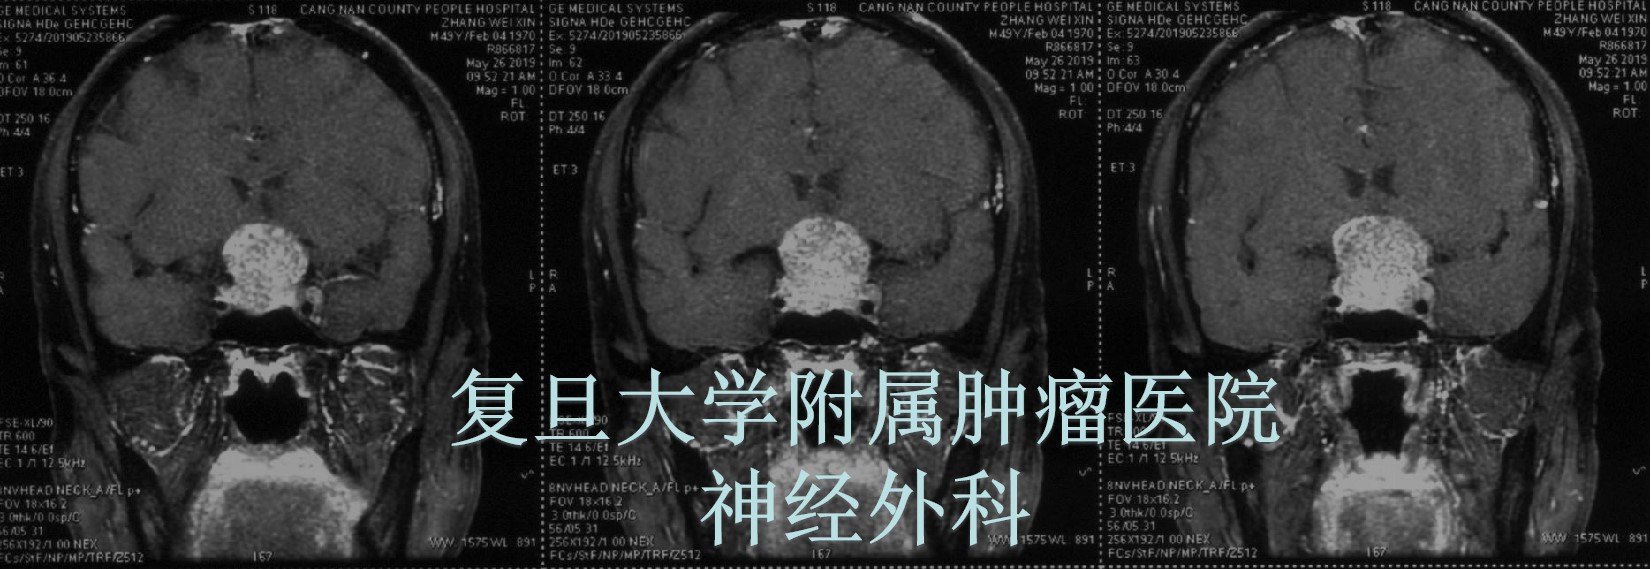

头颅MRI检查提示:鞍区巨大占位性病变,垂体肿瘤。

临床诊断初步考虑:巨大侵袭性垂体瘤。